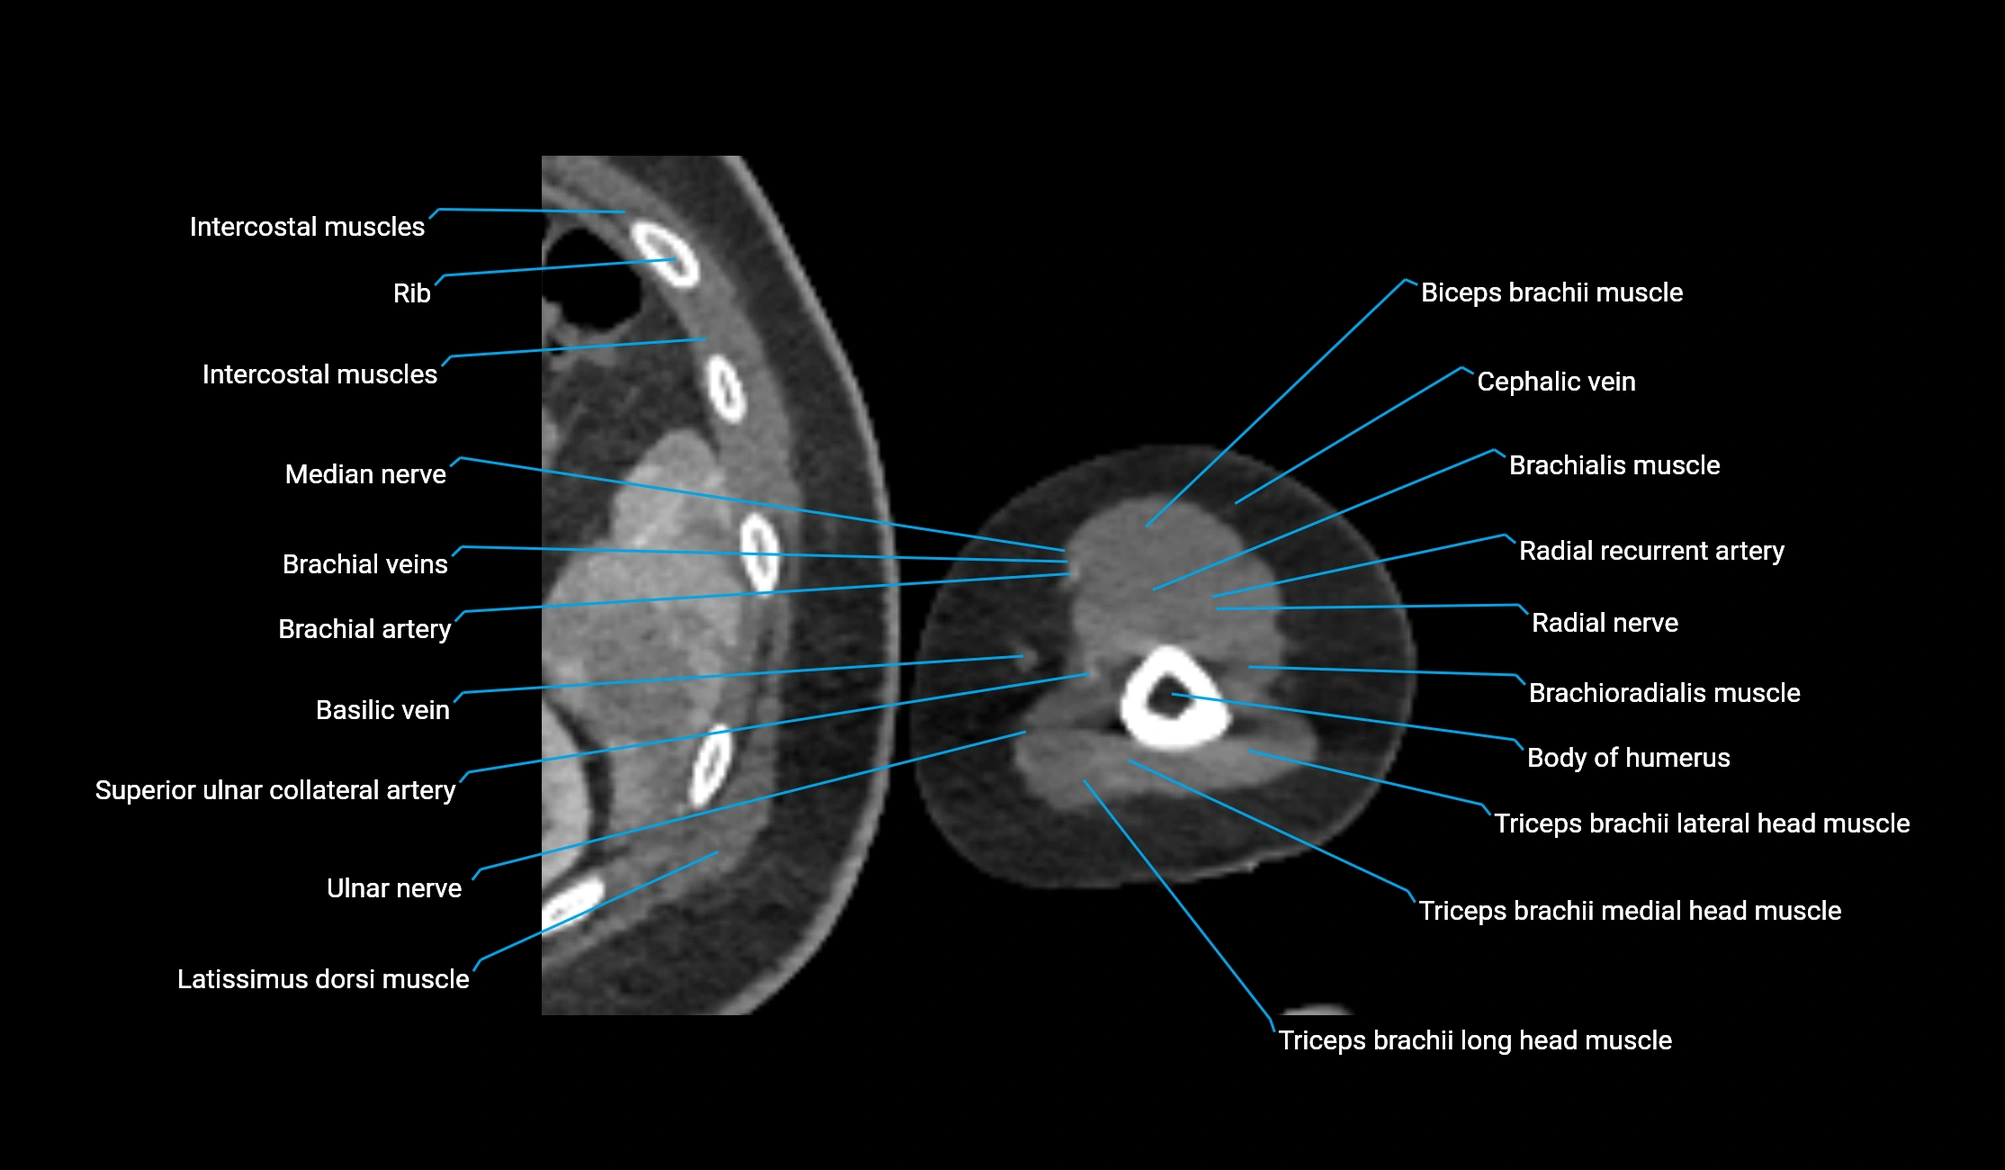

CT image